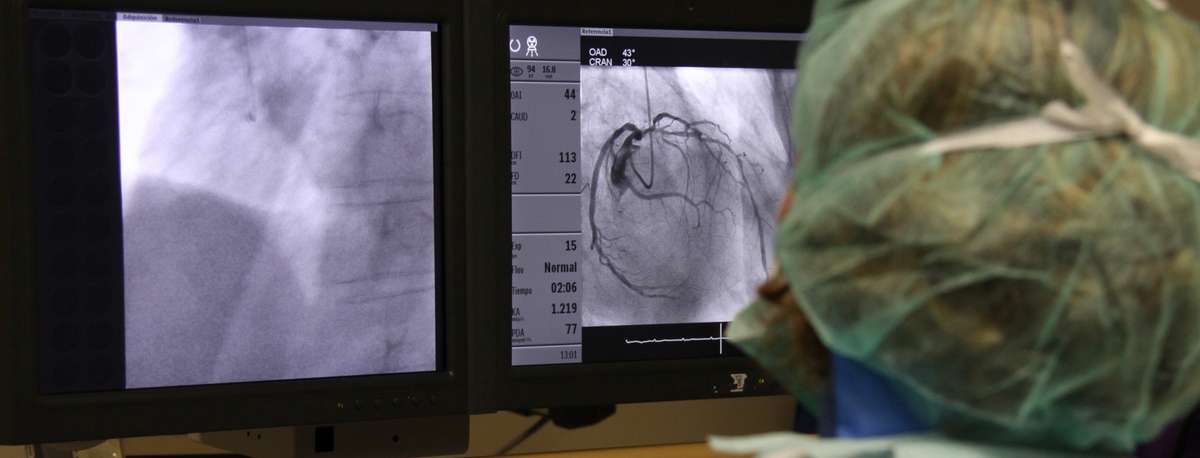

Instituto del Corazón Quirónsalud Teknon

En el instituto contamos con especialistas en Angiología, Cirugía Vascular y Endovascular para el diagnóstico y seguimiento de las enfermedades del aparato circulatorio. La embolia cerebral y el tromboembolismo pulmonar son algunas de las principales causas de muerte debido a un problema vascular.

Nuestro equipo es especialista en técnicas mínimamente invasivas, utilizando técnicas endovasculares, sin cirugía, que permiten implantar prótesis vasculares para resolver dilataciones o aneurismas de las arterias. También ofrecemos todos los tratamientos de la patología venosa y arterial periférica, incluyendo las enfermedades de las arterias carótidas.